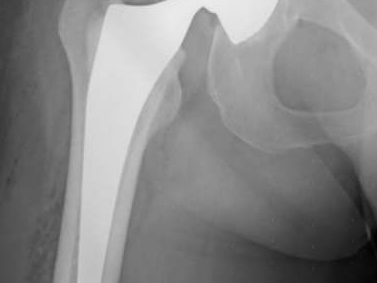

Album photo